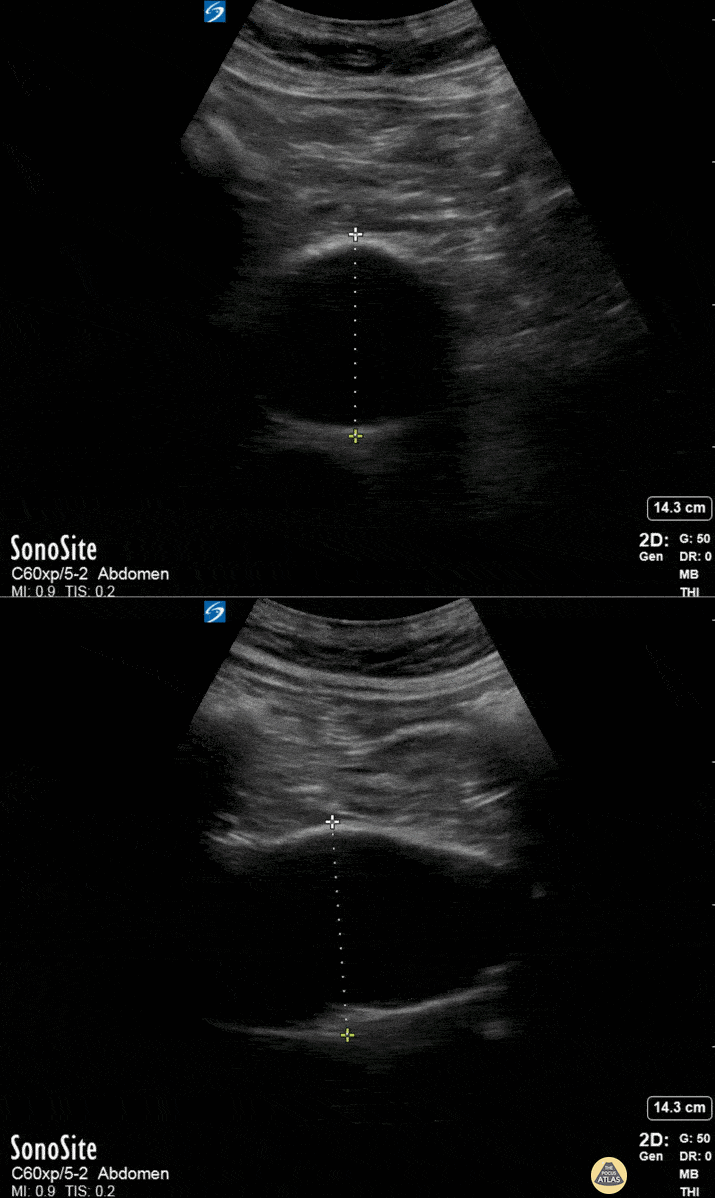

Aorta - Incidental AAA

Routine abdominal evaluation using a Sonosite X-Porte curvilinear ultrasound probe revealed this 6.0cm abdominal aortic aneurysm (without rupture or dissection) in a patient with risk factors for the same. This enabled our middle-aged diabetic male with 80 pack/yr smoking history to receive timely evaluation by vascular surgery and subsequent appropriate serial monitoring and follow-up. Siang-Chean Kua MS-4 Central Michigan University College of Medicine Additional contributors: Ryan Shelby, MD, Thomas Ferreri, MD, Therese Mead, DO, RDMS, FACEP